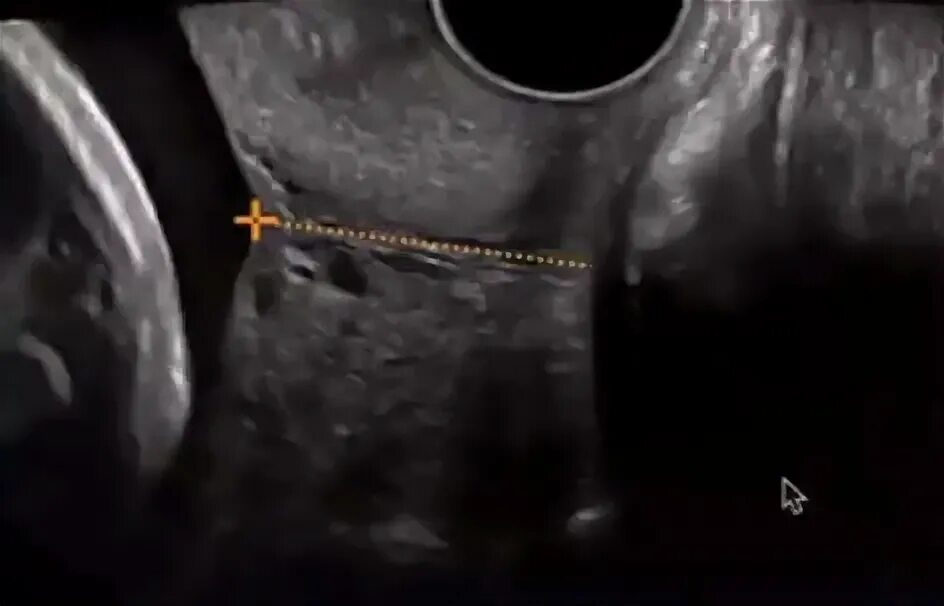

Цервикометрия при беременности как делают